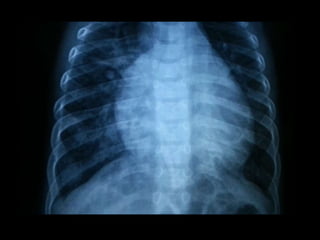

 Radiología: siempre existe cardiomegalia que afecta a

las cuatro cámaras cardiacas. La vascularización

pulmonar esta aumentada y destaca el segmento de

la arteria pulmonar principal

 Radiología: siempreexiste cardiomegalia que afecta a las cuatro cámaras cardiacas. La vascularización pulmonar esta aumentada y destaca el segmento de la arteria pulmonar principal